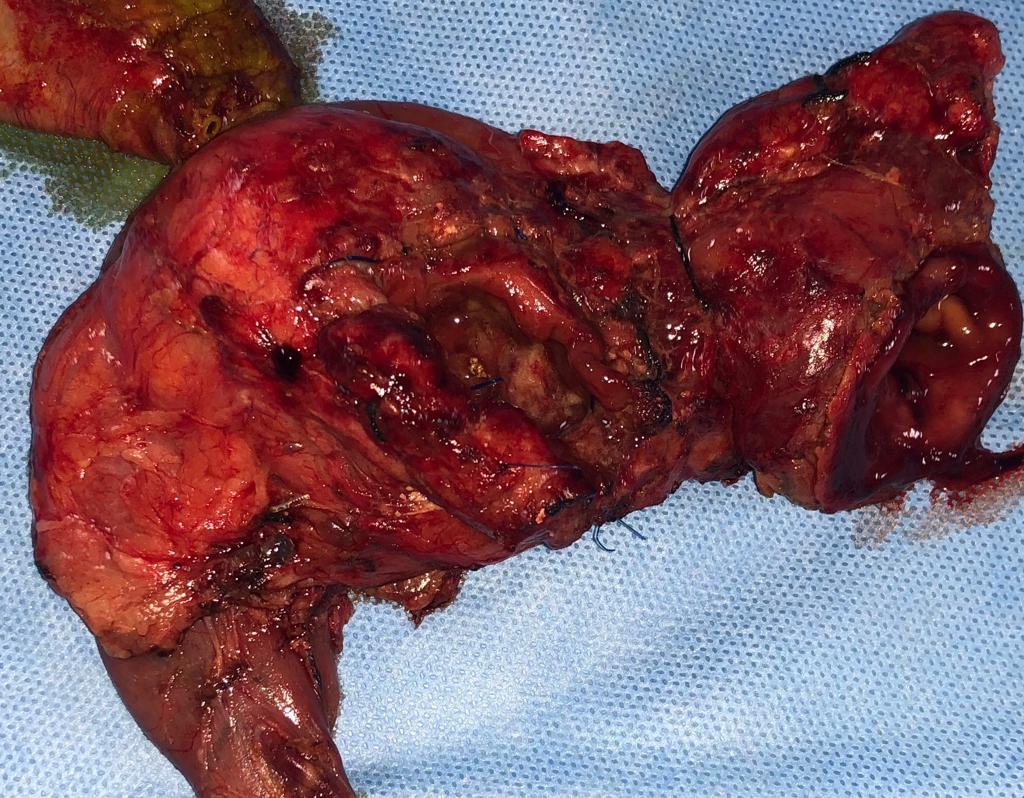

A rare case of a young unmarried female with multiple giant fibroids weighing over 2 Kg

She was diagnosed with uterine fibroids of 7x7 cm in 2019. Her menstrual cycle was regular. But the patient postponed surgery despite the gynaecologist's advice due to COVID and thinking it would subside with medications. After 3 years, ultrasonography showed multiple fibroids. The uterus had grown to the size of 7 month pregnant uterus. Laparoscopic myomectomy and then open myomectomy surgery was performed, and 28-30 fibroids were enucleated. The largest fibroids of 14-15 cm and smallest of 1 cm fibroid were observed. All the fibroids together weighed around 2 kg. All the fibroids were enucleated and the uterus was repaired, as preservation of the uterus is essential for future pregnancy. Patient went home happily.